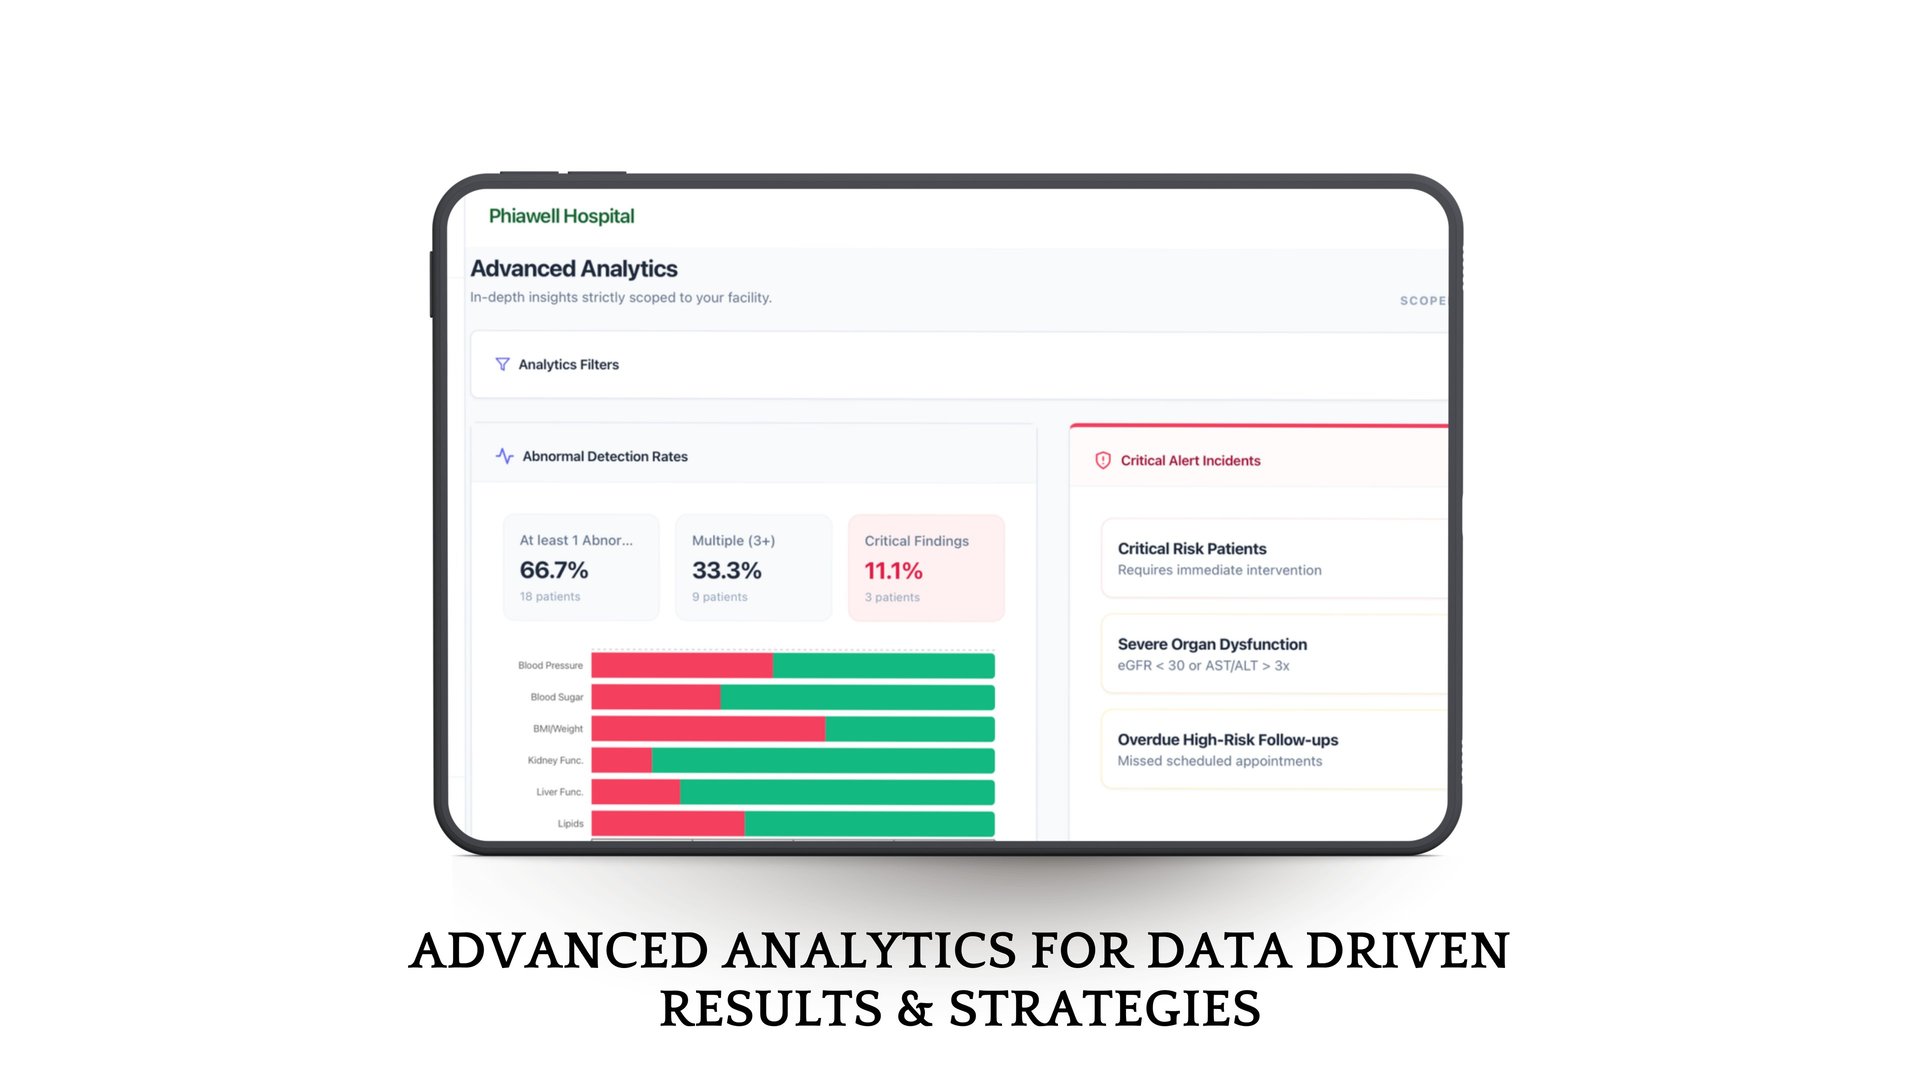

Intelligent Health Insights

With built-in risk assessment, smart analytics, and concise patient summaries, doctors can make faster, more accurate decisions while shifting towards preventive care.

Phia.Care's Risk Assessment Models

Phia.Care's Risk Assessment Models use clinically recognized algorithms, including WHO-based risk evaluation frameworks, to analyze patient screening data and generate structured health risk insights.

By evaluating vitals, demographics, and other screening parameters, the system creates a standardized risk profile for each patient and assigns a confidence score based on data completeness. This helps clinicians quickly understand potential health risks and support early, informed medical decisions.